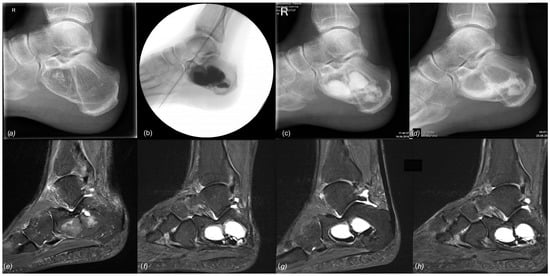

Complications were predominantly related to the use of Cerament©, leading to a 90% complication rate (9/10) in patients treated with this particular injectable bone substitute. These complications included DWH with “white-out” in 7/10 cases, one case of DWH without “white-out”, one revision surgery, and one suralis neuropraxia. As the “white-out” phenomenon has been repeatedly observed in various non-tumorous indications in our clinical practice, and excessive white drainage after the use of Cerament© does not seem to be limited to its use in aneurysmal bone cysts, we have stopped using this product entirely. Figure 9 and Figure 10 show examples of the gradual loss of Cerament© over time, leading to “white-out”, insufficient stabilization of the bone cavity, and cyst recurrence. These specific complications did not occur with other injectable bone substitutes. However, repeated MRI performed after treatment with two different types of calcium phosphate bone cement (case 6 and 25, Quickset© and Innotere©) did not demonstrate any postoperative signs of osseous ingrowth or bony transformation at 36 and 91 months (Figure 6b and Figure 11), respectively.

Figure 9.

Top, left to right: (a) preoperative X-ray of a large IOL, Milgram Stage 3 (case 22); (b) intraoperative fluoroscopy, postoperative radiographs at 6 (c) and 12 (d) weeks postoperatively showing continued loss of the filling material, consistent with persistent wound drainage. Bottom, left to right: (e) preoperative MRI, (f) sagittal MRI 12 months postop, (g) 20 months postop, and (h) 32 months postop. All MRI are sagittal T1 TIRM weighted.